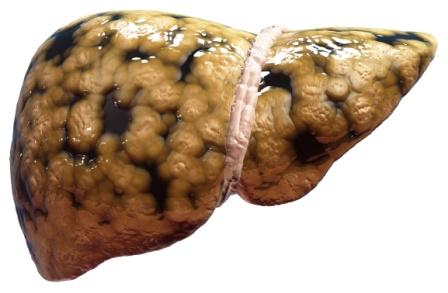

The tricky thing about fat is that, it can accumulate underneath the skin (to cause obesity) and also in some organs. Liver is one such organ wherein excessive fat accumulation can lead to a condition called Fatty liver disease or Steatosis.

Some amount of fat is normally present in the liver. But when the quantity of accumulated fat increases so as to contribute to more than 5-10% of its weight, the condition is known as Fatty Liver Disease.

It is a condition in which the liver cells accumulate abnormally increased amounts of fat. Excessive consumption of alcohol is a very common cause of Fatty Liver.

It is a reversible condition wherein large vacuoles of triglyceride fat accumulate in liver cells via a process of steatosis (abnormal retention of lipids within the cell).

FLD is associated with other diseases that influence fat metabolism. When this process of fat metabolism is disrupted, the fat can accumulate in the liver in excessive amounts, thus resulting in fatty liver. Accumulation of fat may also be accompanied by a progressive inflammation of the liver (hepatitis) called steato-hepatitis.

Pathology of fatty liver

Fatty changes represent the accumulation of triglycerides (neutral fats) in the cytoplasm of liver cells.

- Initial changes: Hepatocytes present small fat vacuoles (liposomes) around the nucleus (micro-vesicular fatty change). Here liver cells are filled with multiple fat droplets.

- Late stages: Size of the vacuoles increases, nucleus is pushed to the periphery of the cell giving a characteristic ‘signet ring’ appearance (macro-vescicular fatty change). These vesicles are well delineated and optically empty because fats dissolve during tissue processing. Large vacuoles may coalesce and produce fatty cysts which are irreversible lesions.

- Macro-vescicular steatosis is the most common form. It is typically associated with alcohol, diabetes, obesity and corticosteroids.

- The diagnosis of steatosis is made when fat in the liver exceeds 5-10% by weight